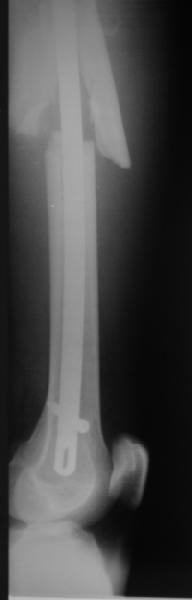

Уважаемые коллеги! От имени Алексея Смирнова всем спасибо за обсуждение. Больной прооперирован. Снимки в приложении.

Мы бы не стали открывать, такие переломы срастаются, хотя бы и с краевым дефектом. То есть если удалять стержень потом, то сильно попозже обычного. В приложении пример. Сразу после операции и через 11 мес. Понятное дело, пациент к тому времени давно и не хромал, и функция колена была полная.